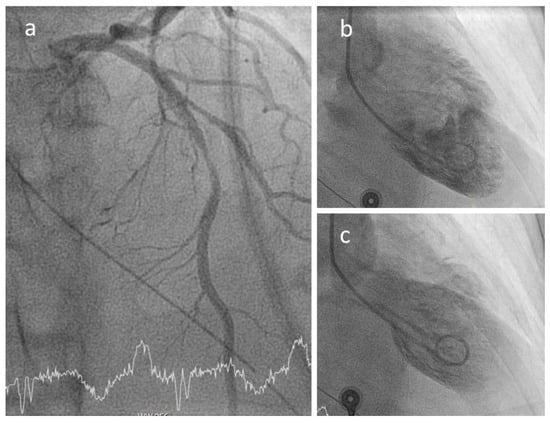

At angiography, coronary artery vasculitis may manifest under the form of coronary stenosis, aneurysm (Figure 2), dissection (Figure 3, most frequent in eosinophilic periarteritis), spasm (Figure 4), or coronary rupture (Table 1). Sudden death, typical angina, acute myocardial infarction, atrial and ventricular arrhythmias, conduction disturbances, or cardiac failure have all been described []. Although no specific finding at coronary angiography allows a safe diagnosis, features associated with early, advanced, or atypical coronary artery disease may suggest an inflammatory etiology. For example, Kawasaki disease and polyarteritis nodosa are often associated with large aneurysms []. Polyarteritis nodosa often features multifocal aneurysms with a “beads on a string” or nodular appearance [], which are also present in patients with anti-neutrophil cytoplasmic antibody (ANCA)-associated vasculitis and Behcet’s disease []. The arterial lesions in Behçet disease may be occlusive or aneurysmal []. Giant cell arteritis has been associated with long coronary lesions [], and in Takayasu’s arteritis, coronary lesions have been classified in three main types: 1, stenosis or occlusion of the coronary ostia (60–80%); 2, diffuse disease that may involve all epicardial branches or only focal segments (10–20%); and 3, coronary aneurysms (0–5%) [].

Figure 4.

Coronary spasm in a 51-year-old female patient with ANCA-associated vasculitis and spasm of the proximal left anterior descending (panel a) causing a Tako-Tsubo-like contractile dysfunction (b,c).